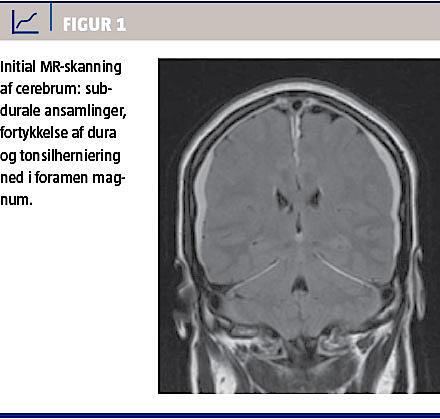

MR-skanningen (Figur 1) viste bilaterale subdurale ansamlinger, fortykket dura, dilaterede brovener og kaudal displacering af cerebrum med affladning af de basale cisterner, men ingen tegn på sinustrombose. På den medskannede del af columna cervicalis kunne der ses ekstradurale væskeansamlinger, som gav mistanke om en dural likvorfistel på C1-C2-niveau.

Den egentlige patogenese diskuteres stadig indgående, men den momentane effekt af ovenstående indgreb tyder på, at udsivning af likvor har en sammenhæng med SIH. Hos kvinden i sygehistorien viste en MR-skanning af cerebrum – forud for blood patch-anlæggelsen – forandringer, som var forenelige med SIH (Figur 1). På kontrolskanningen otte måneder senere var der normalisering af de intrakraniale forhold og ingen tegn på spinal likvorfistel. Det må derfor antages, at blood patch’en, som medførte en klar symptombedring, har været med til at forsegle likvorfistlen, hvilket resulterede i det benigne kliniske forløb og kontrolskanningens normale anatomiske forhold.